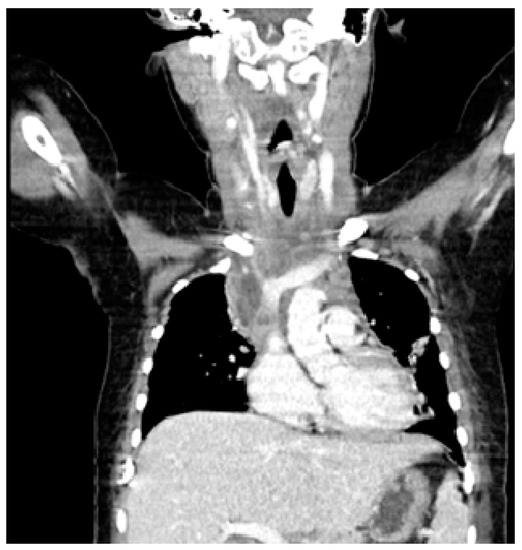

On the fourth day of admission a GAS was isolated from a blood culture and IV clindamycin was added to her treatment. When repeated to include the cervical area, in addition to the known mediastinal lesions, a CT scan revealed edema and densification of the retropharyngeal space, suggesting a descending mediastinits extending from a cervical infection (Figure 2). There was no air suggestive of an esophageal perforation.

Figure 2. Neck and Chest CT Scan.